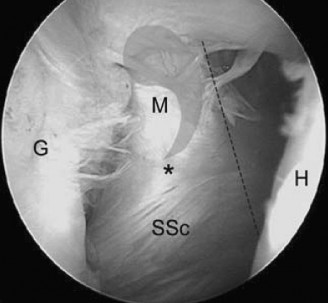

The correct answer is (A). When a chronic, retracted subscapularis tendon tear is present, the superolateral border of the tear can be identified by a comma-shaped ligamentous structure that exists at this border. This is composed of an avulsed superior glenohumeral ligament blending with the coracohumeral ligament and is called the comma sign (see Fig. 2–12).

_Figure 2–12_Comma sign, indicating the superior border of a chronic, retracted subscapularis tendon tear. G, glenoid; H, humerus; SSc, subscapularis; M, medial sling of biceps (comma); , junction of medial sling of biceps and subscapularis tendon. (Redrawn from Burkhart SS, Lo IKY. Arthroscopic rotator cuff repair. J Am Acad Orthop Surg. 2006;14(6):333–346.)